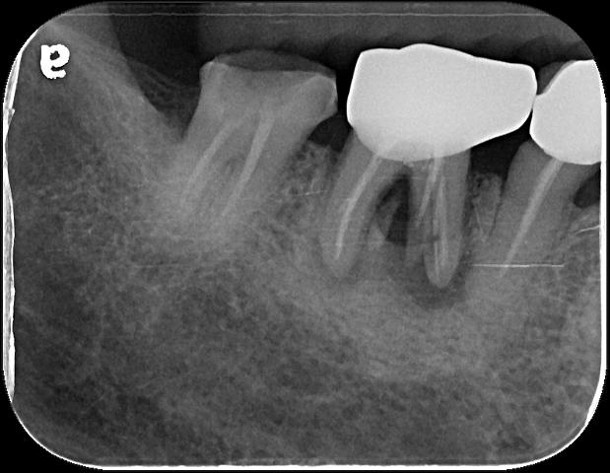

治療前,蛀牙齒質破壞

治療前,患者已接過根管治療

治療後根尖片